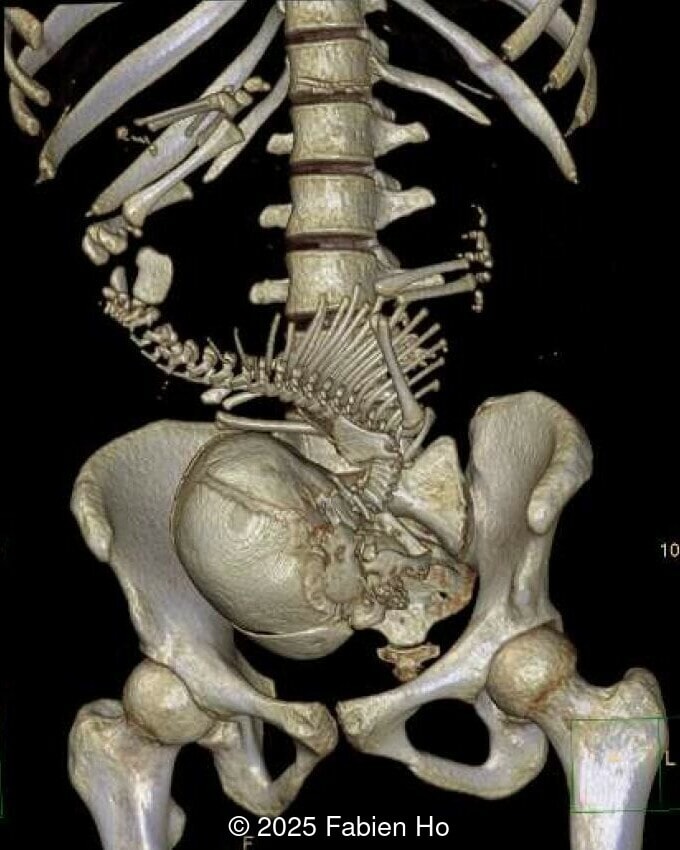

At 36 weeks gestation, the abdominal findings were unchanged however, the bones appeared short (<1st percentile) and the spine had an unusual appearance, therefore a computed tomography was performed at 37 weeks gestation.

Our prenatal ultrasound revealed a male fetus with megabladder, dilation of both ureter and kidneys, and thinned kidney parenchyma consistent with Lower Urinary Tract Obstruction (LUTO).  Additional findings suspected on ultrasound and confirmed on computed tomography included:

• Short long bones (<1st percentile), normal mineralization, and no sign of lethal chondrodysplasia

• Dysostosis: Hemivertebrae L3, fused L4-L5, abnormal left foot with short metatarsals and missing phalanges

The couple chose to deliver naturally. After prenatal needle aspiration of the bladder, the baby was delivered at 39 weeks gestation. Postnatal findings were consistent with Prune-Belly Syndrome with flaccid abdominal wall (similar to prune skin), lower urinary tract obstruction in a male fetus, imperforate anus requiring colostomy, lumbar hemivertebrae, and left foot hypoplasia including metatarsals and phalanges.